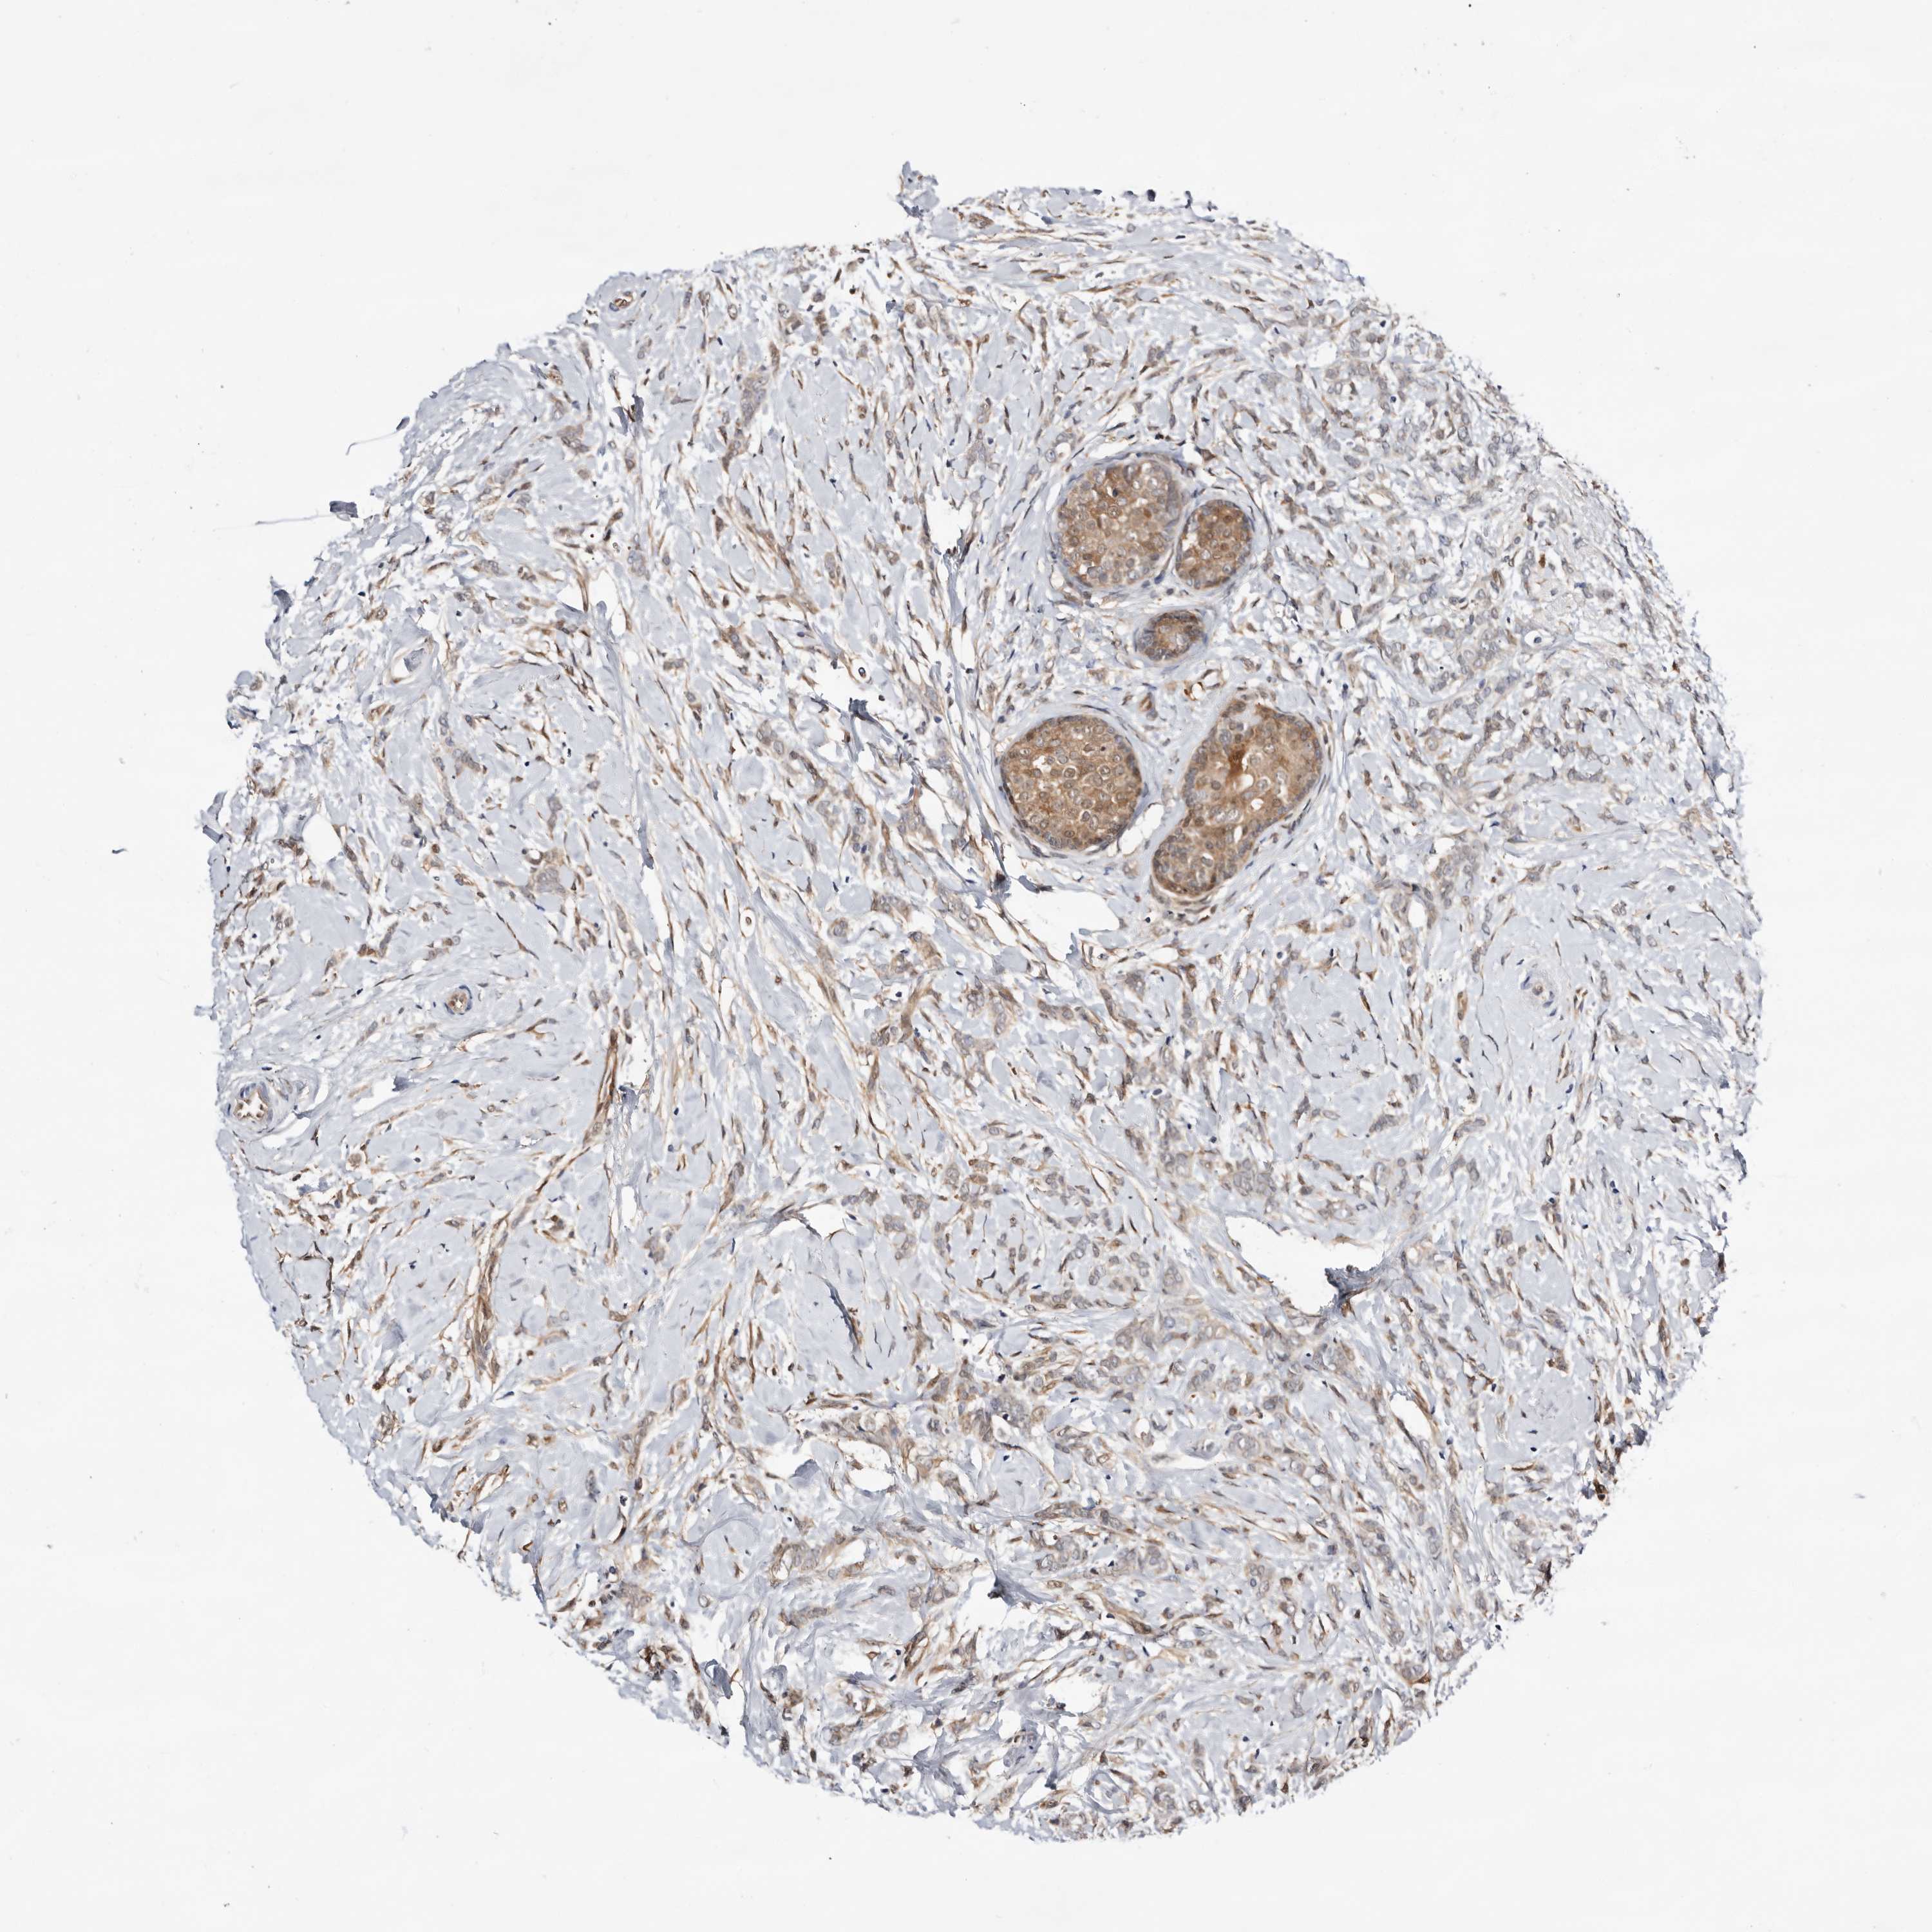

BRCA TCGA BRCA VALIDATION PROTEIN EXPRESSION

ANTIBODIES

AND

VALIDATION